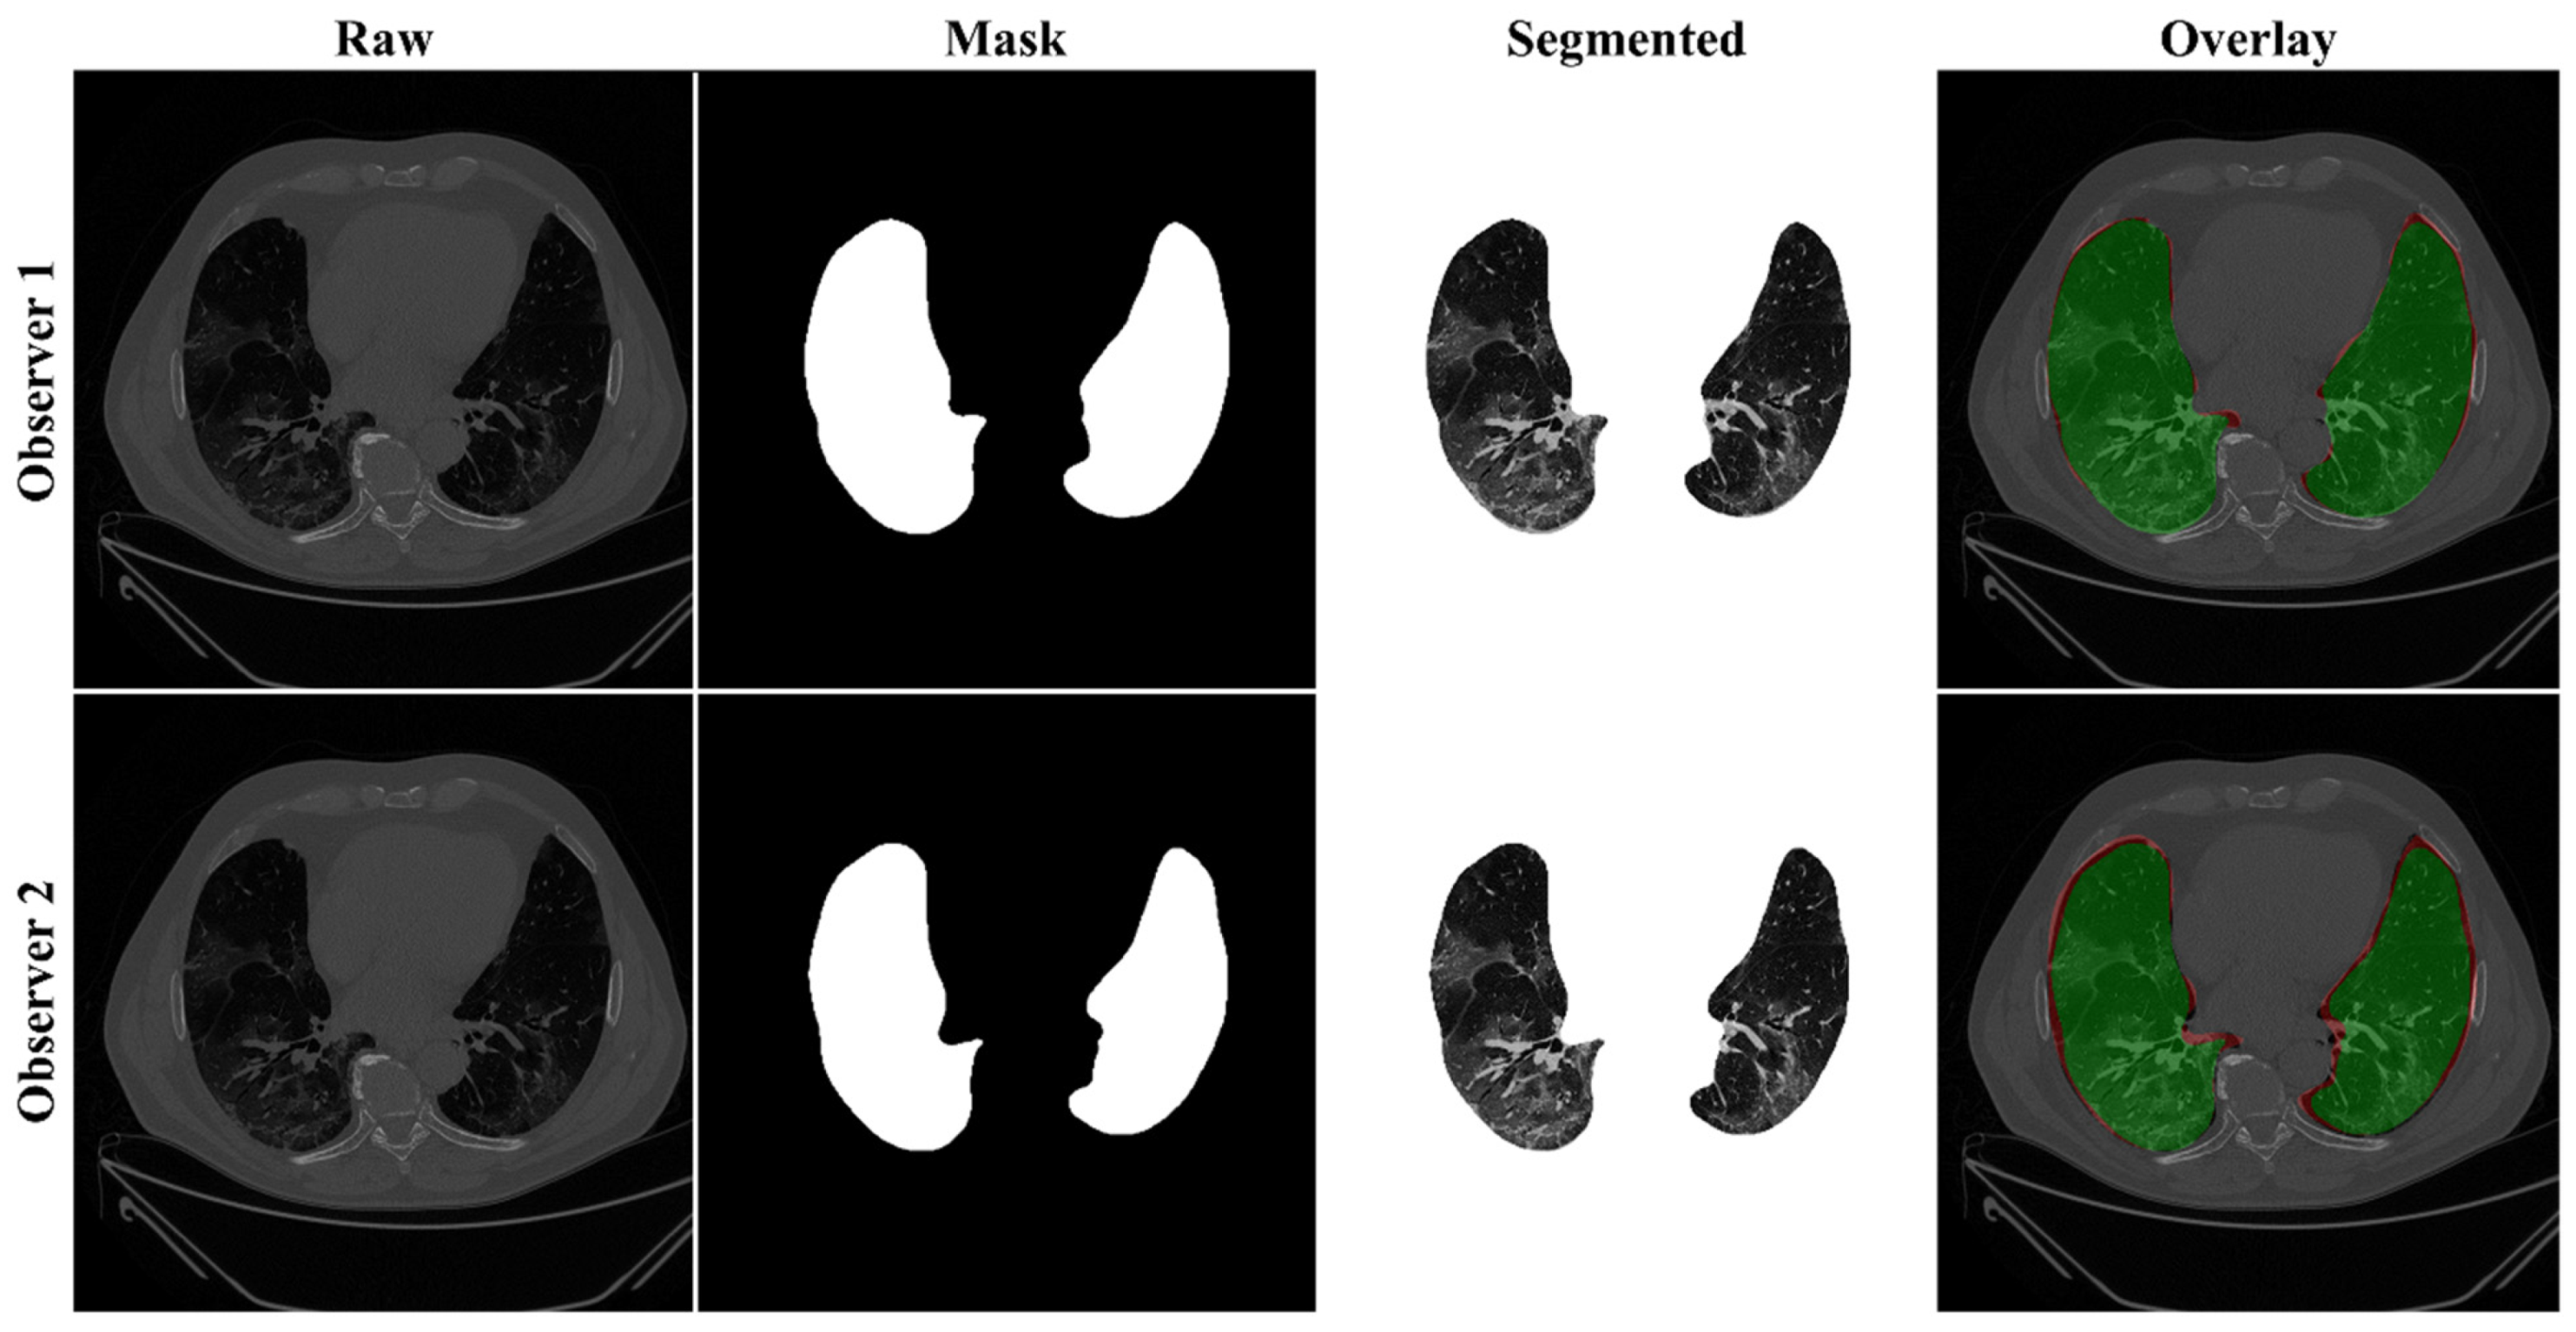

4.2.1. Lung Boundary and Long Axis Visualization